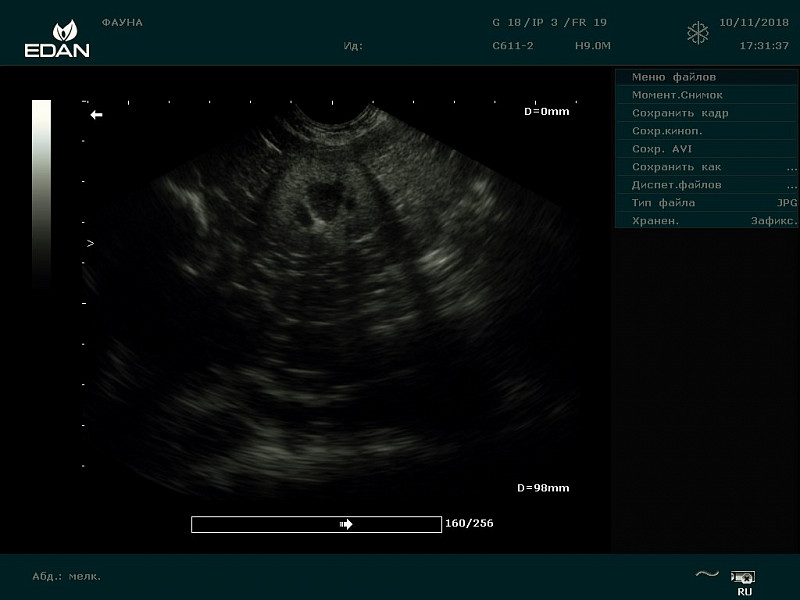

Через неделю сделали УЗИ почек:

Правая: корковый слой - 7,5 мм, мозговой слой - 10,2 мм. Р-ры: длина - 28,8 мм, высота - 26 мм.

Левая: корковый слой - 5,57 мм, мозговой слой - 9,61 мм. Р-ры: длина - 30 мм, высота - 19,8 мм.